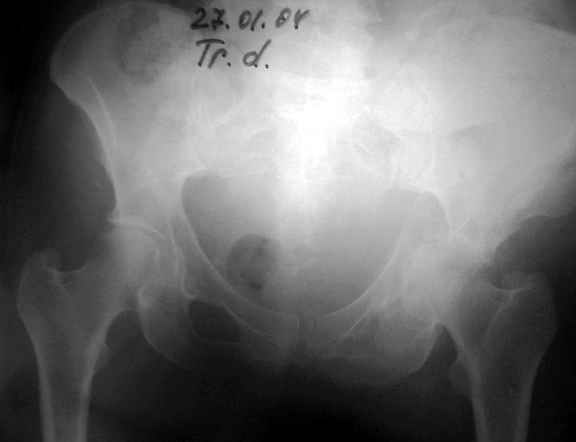

Anatoly F Lazarev 03 Сентябрь 2004, 22:18

27.01.04

02.02.04

10.02.04

12.04.04

02.06.04